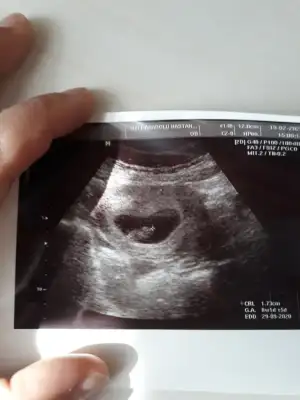

Banada tahminde bulunurmusunuz 8 haftalik burda

Eklentiler

• 20200223_135237.webp

20200223_135237.webp

25,2 KB · Görüntüleme: 270